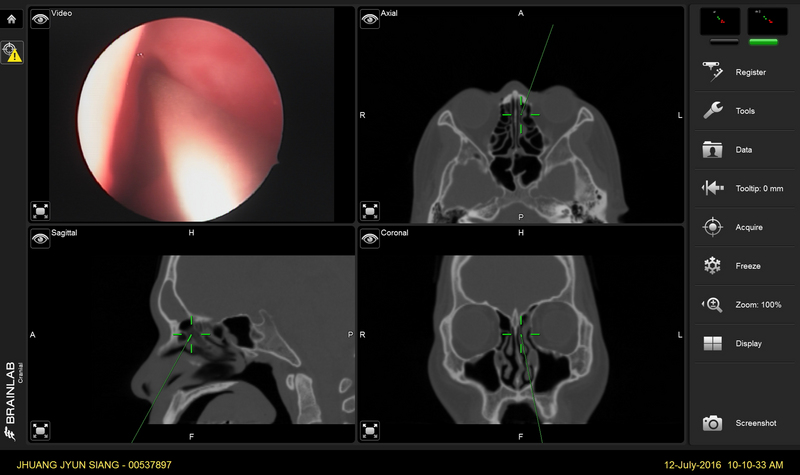

張進芳說明,目前治療慢性鼻竇炎的主流是微創手術,即所謂的功能性內視鏡鼻竇手術(FunctionalEndoscopic Sinus Surgery,簡稱FESS),它是利用內視鏡的方式將嚴重病變的組織(例如鼻息肉或黴菌球)去除,並恢復鼻竇開口通暢,使鼻竇內纖毛的功能恢復正常。

此外,功能性內視鏡手術的適應症除了慢性鼻竇炎、急性鼻竇炎併眼或腦部併發症的處理外,前顱底腫瘤、鼻腔內腫瘤切除手術,及腦脊髓液滲漏的修補等手術皆可藉由內視鏡的輔助以微創的方式進行。(轉自中央社)